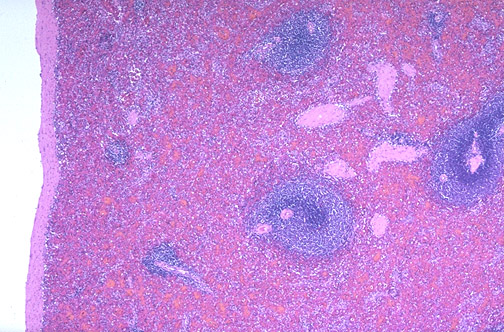

| This is the normal appearance of the spleen at low power with white pulp (lymphocytes) surrounding a central arteriole. The red pulp forms the bulk of the splenic parenchyma. The splenic capsule is seen at the left, and connective tissue is also present within the spleen as trabeculae that carry the arteries, veins, and nerves from the hilum. |